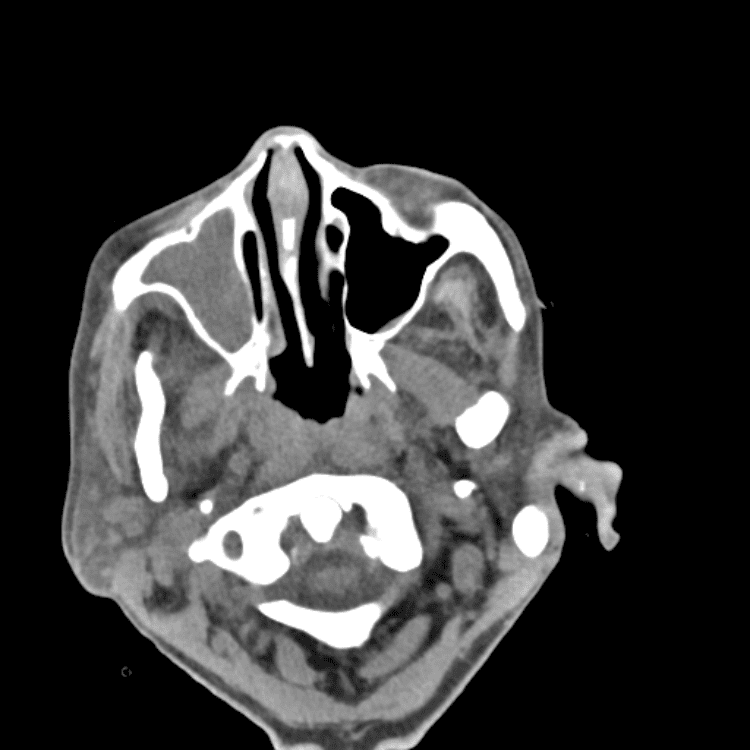

Head and Neck

Practice

Simulates call by including subtle or difficult cases and some normals.

27 cases